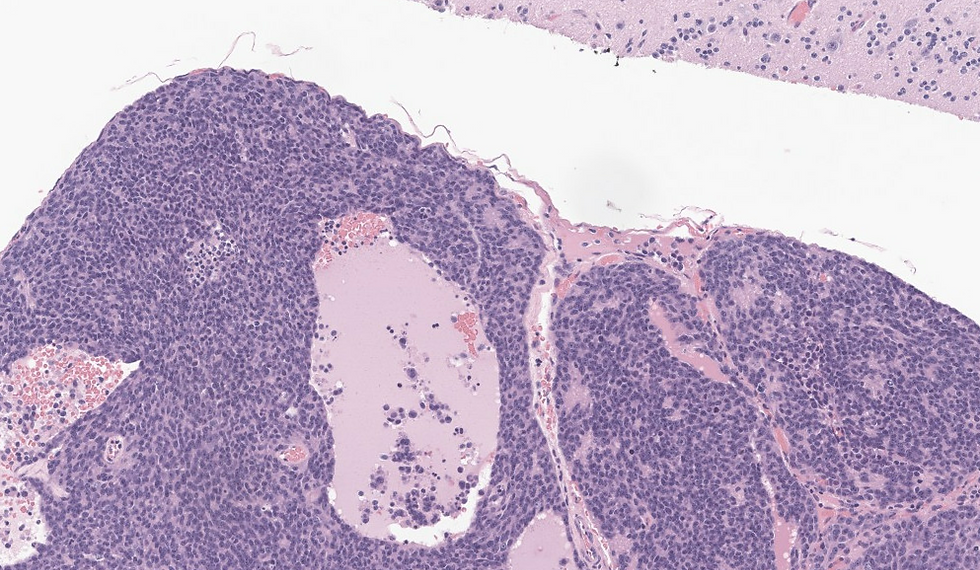

This case is Olfactory neuroblastoma but the above lists are good differentials in small round cell tumors in sinonasal tract. Olfactory neuroblastoma derived from immature or progenitor olfactory epithelium cells and are arranged in nests, lobules, or sheets that are clearly delineated by a rich vascular stroma, usually in the submucosa. A salt-and-pepper nuclear chromatin characterizes the cells. In ONBs, fibrillary cytoplasm and interdigitating neuronal processes (neuropil) are characteristic. Flexner–Wintersteiner rosettes and Homer Wright pseudorosettes can be seen. High-grade tumours show a more sheet-like growth pattern. Rosettes by themselves are not diagnostic of ONB, although Homer Wright pseudorosettes with neuropil are nearly pathognomonic in the nasal cavity. In this case there are vaguely cules of Homer Wright pseudorosettes that does not have a true lumen without a cytoplasmic extension. ONB are typically positive for neuroendocrine markers and negative for keratin (1/3 can be positive). On the other hand, neuroendocrine neoplasms are always positive for keratin. SSTR2A can be positive in ONB. An important ddx here is sinonasal undifferentiated carcinoma, which are negative for neuroendocrine markers.